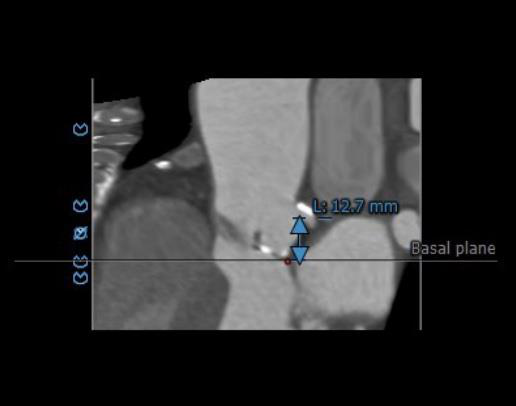

左右冠开口高度可,右冠多发钙化,依据瓦氏窦宽度和瓣叶长度预估右冠风险较小,左冠存在堵塞风险。

瓦氏窦内径、窦管交界内径偏小。升主内径尚可,主动脉瓣环与水平面夹角可,主动脉弓角度与宽度可。

左右冠开口高度可,右冠多发钙化。

瓦氏窦内径可、窦管交界内径可。升主内径可,主动脉瓣环与水平面夹角可,主动脉弓角度与宽度可。